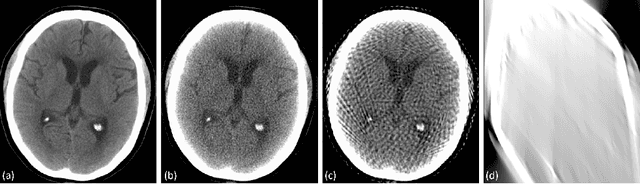

Abstract:Automated medical image classification with convolutional neural networks (CNNs) has great potential to impact healthcare, particularly in resource-constrained healthcare systems where fewer trained radiologists are available. However, little is known about how well a trained CNN can perform on images with the increased noise levels, different acquisition protocols, or additional artifacts that may arise when using low-cost scanners, which can be underrepresented in datasets collected from well-funded hospitals. In this work, we investigate how a model trained to triage head computed tomography (CT) scans performs on images acquired with reduced x-ray tube current, fewer projections per gantry rotation, and limited angle scans. These changes can reduce the cost of the scanner and demands on electrical power but come at the expense of increased image noise and artifacts. We first develop a model to triage head CTs and report an area under the receiver operating characteristic curve (AUROC) of 0.77. We then show that the trained model is robust to reduced tube current and fewer projections, with the AUROC dropping only 0.65% for images acquired with a 16x reduction in tube current and 0.22% for images acquired with 8x fewer projections. Finally, for significantly degraded images acquired by a limited angle scan, we show that a model trained specifically to classify such images can overcome the technological limitations to reconstruction and maintain an AUROC within 0.09% of the original model.